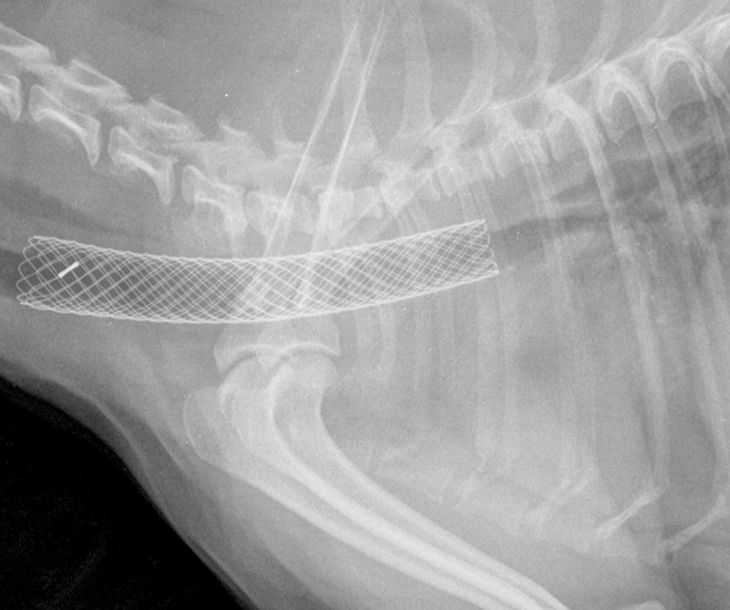

기관 스텐트

기관지 붕괴를 치료하기 위한 하나의 방법으로 스텐트 장착 술이 있습니다. 이는 기관지 내부에 특수제작된 지지대를 삽입하여 공기 흐름을 원활하게 하고 기관지를 개방시키는 치료법입니다. 특히 기관지의 특정 부분에 적용되며, 다이나믹 혹은 스태틱 협착이 있는 경우에 효과적입니다. 스텐트는 주요 기관지나 엽 기관지의 협착 부위에 맞게 설계되어, 해당 기관지의 정상적인 기능을 회복시키는 데 도움을 줍니다.